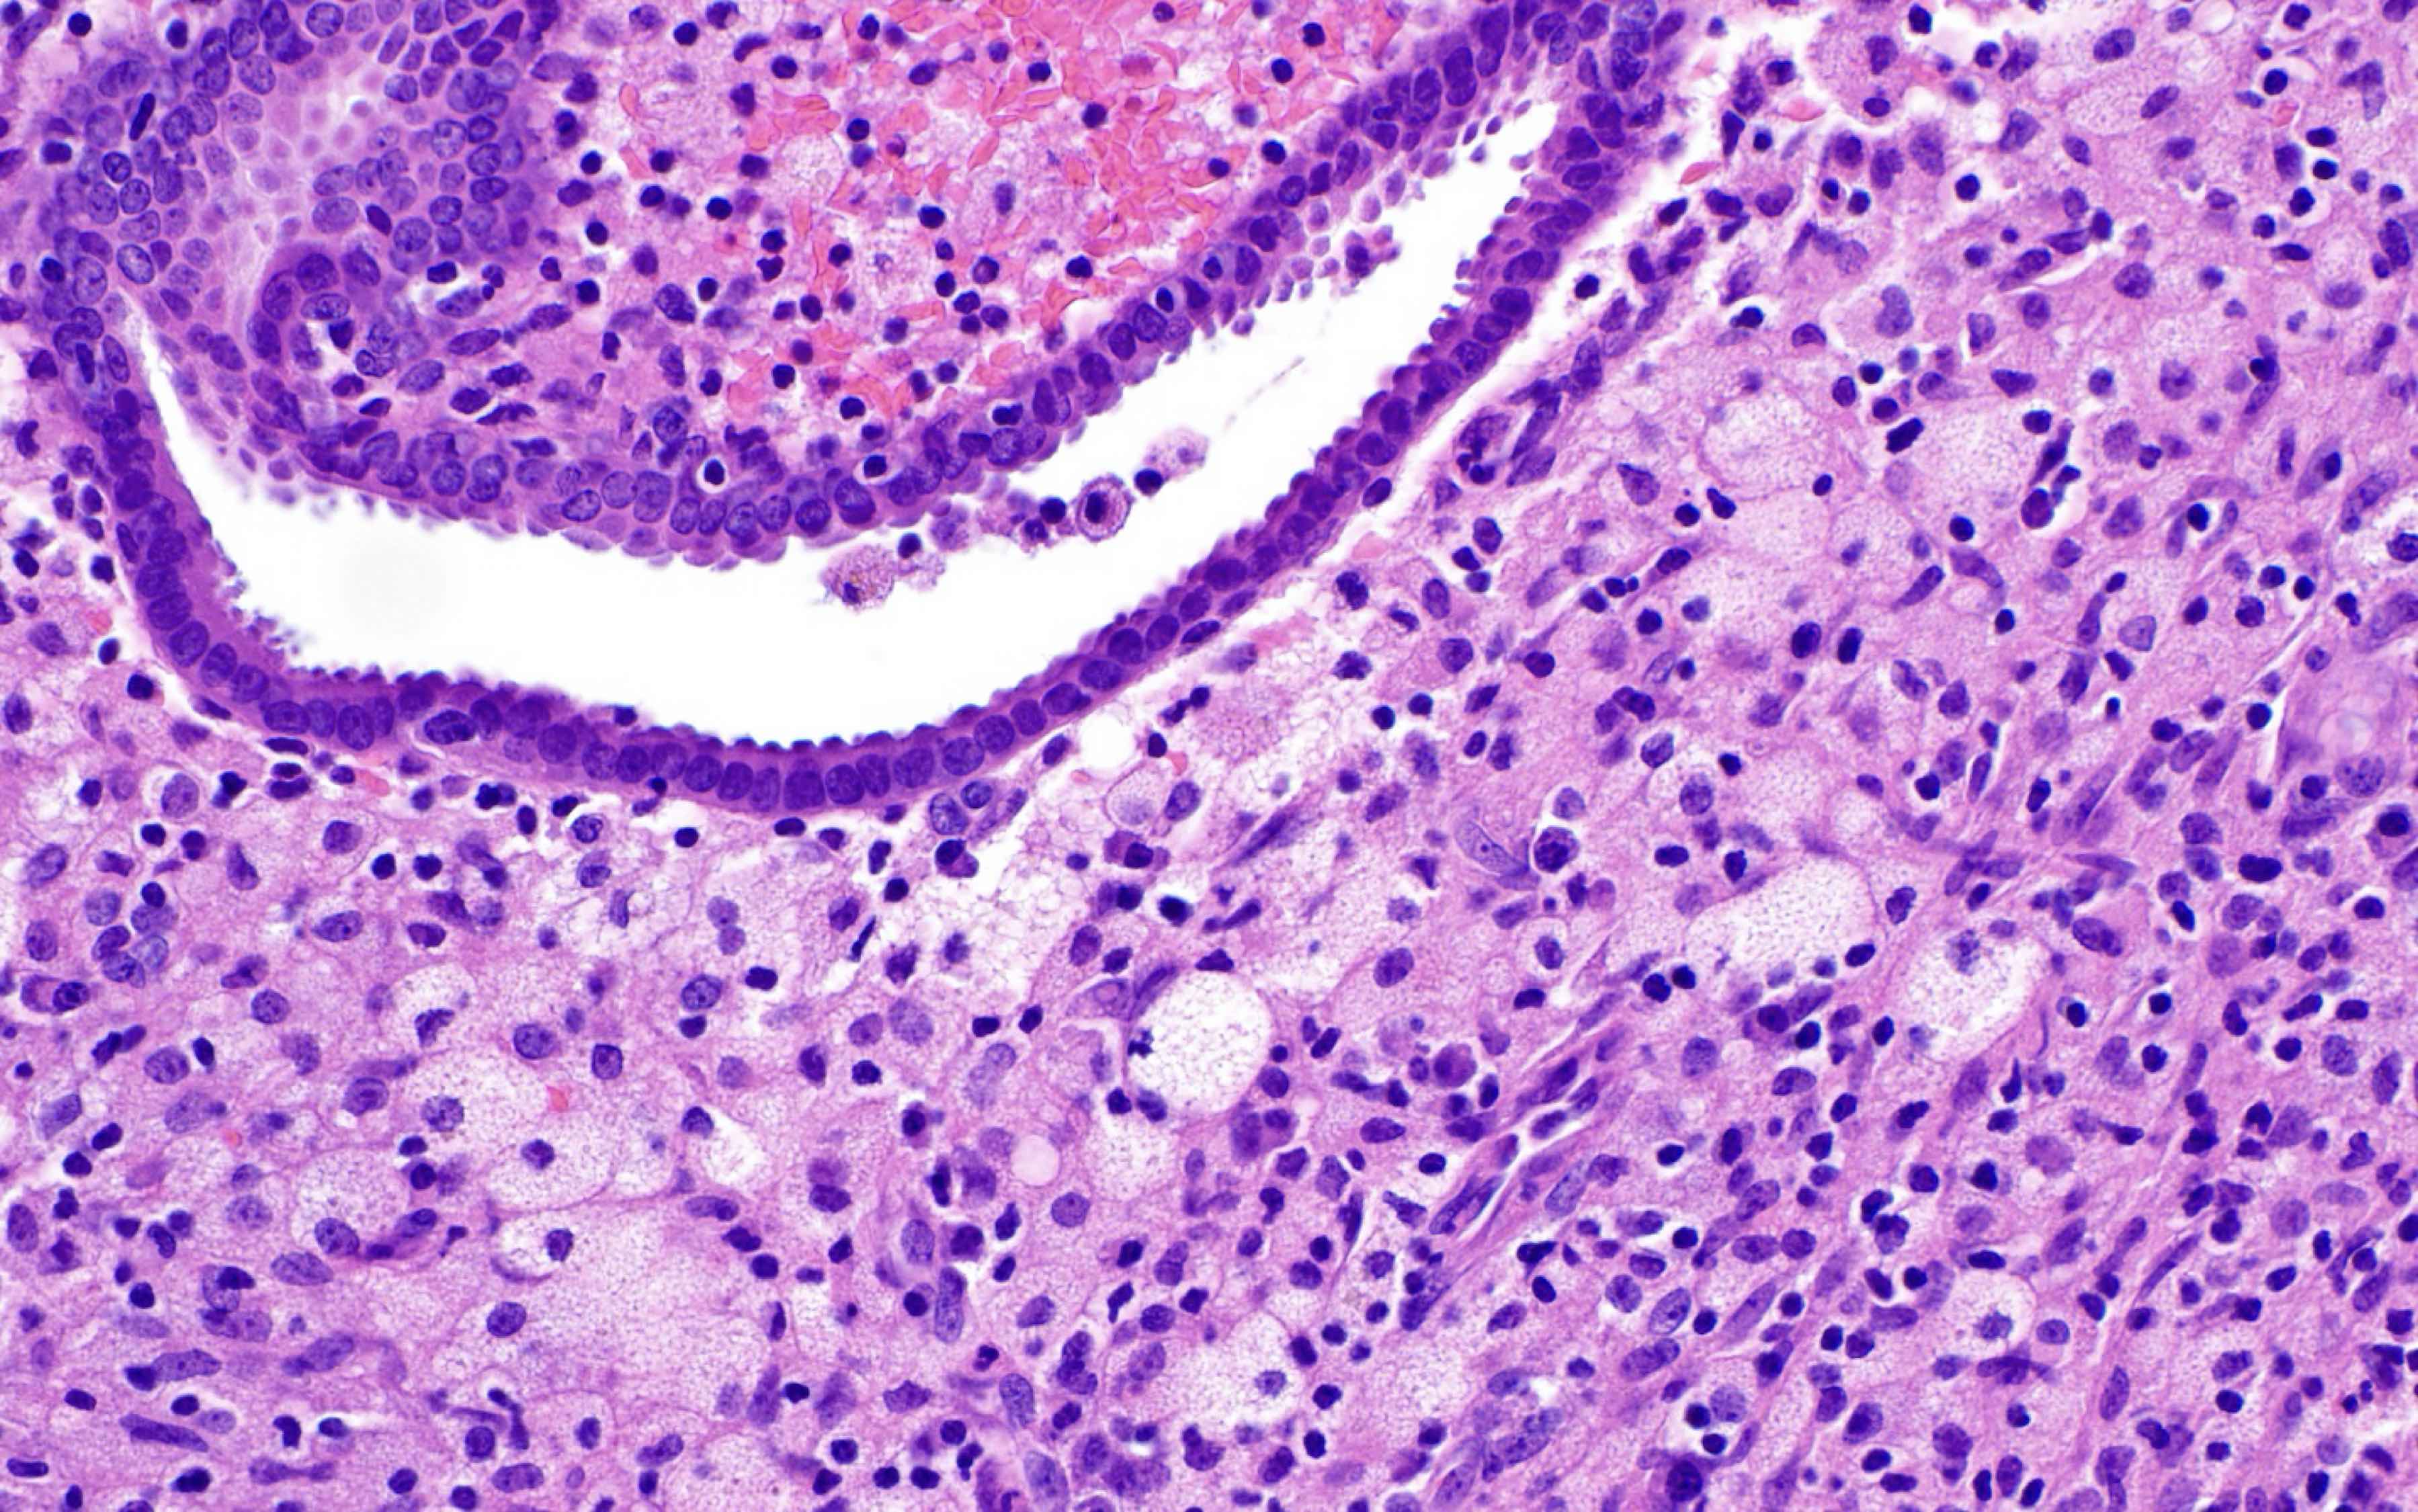

- Xanthogranulomatous endometritis

- Abundant foamy histiocytes, siderophages, neutrophils, plasma cells, lymphocytes

- With or without fibrosis, calcification

Microscopic (histologic) images

Contributed by Stephanie L. Skala, M.D. and Yuri Tachibana, M.D.

Chronic endometritis

Xanthogranulomatous endometritis